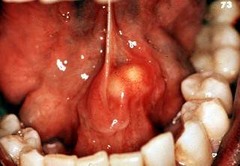

mucocele

-localized tissue swelling that increases and decreases in size most commonly on lower lip -severed salivary gland duct -mucous filled